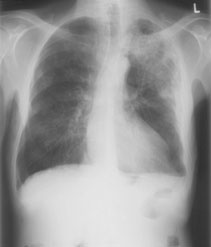

Ihnen wird ein 62-jähriger Patient vorstellig, der seit zwei Wochen subfebrile Temperaturen hat, Husten und leichter Auswurf bestehen ebenfalls. Status nach Zystekomie und Ileum-Pouch sowie Prostatovesikulektomie vor knapp zweieinhalb Jahren bei Plattenepithelkarzinom der Harnblase (pT2 G3).

Klinisch zeigt der Patient einen stabilen Allgemeinzustand. Die Lungenauskultation ist unauffällig. Im Labor ist das CRP auf über 160 mg/l erhöht. Das Thoraxröntgen ergibt folgendes pa Bild:

Thorax pa